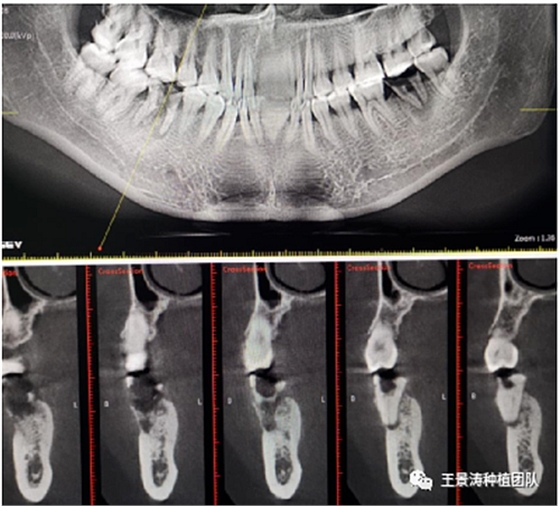

下述病例則是15區(qū)域的即刻種植,15因牙冠折斷于齦下,無法樁核冠修復(fù),則考慮種植修復(fù)。但拍攝CBCT后發(fā)現(xiàn)根尖距上頜竇底距離較短。患者為年輕女性,無全身系統(tǒng)疾病且可利用上頜竇底與根尖皮質(zhì)骨雙側(cè)皮質(zhì)骨固位,且此位置可通過頰側(cè)軟組織減張技術(shù)獲得嚴(yán)密封閉牙槽窩。因其根尖距上頜竇距離較低,遂拔除15后行上頜竇內(nèi)提升,埋入式種植,最終修復(fù)的完成。

左側(cè)下頜第二磨牙及右側(cè)下頜第一磨牙同時(shí)即刻種植病例?;颊吣贻p女性,無系統(tǒng)性疾病。37及46殘冠及殘根,且46劈裂,無法冠修復(fù),必須拔除。37根尖慢性炎癥,大量肉芽組織存在,46根分叉較高,根分叉骨質(zhì)尚可。CBCT示:根尖骨質(zhì)至下牙槽神經(jīng)管距離可滿足種植體的初期穩(wěn)定性,遂考慮即刻種植,并在種植體周邊填入骨粉并覆蓋骨膜,雙側(cè)的種植體初期穩(wěn)定性相差無幾,但考慮到37根尖慢性炎癥較大,遂給予埋入式種植。